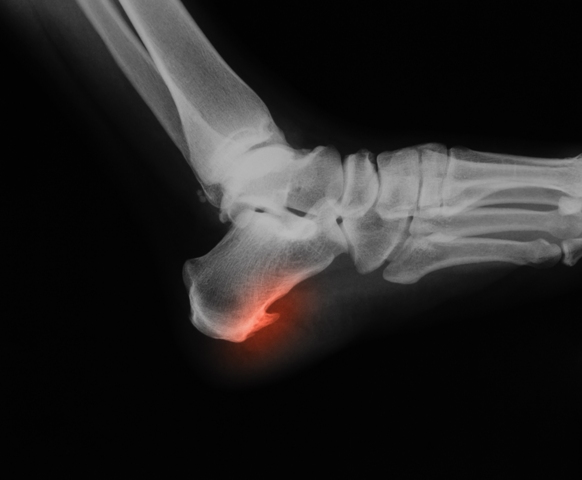

Plantar fasciitis is an inflammation of the plantar fascia of the foot and may be located at insertion into the calcaneus (heel bone) or under the arch.

- -Referral for X-Ray, ultrasound